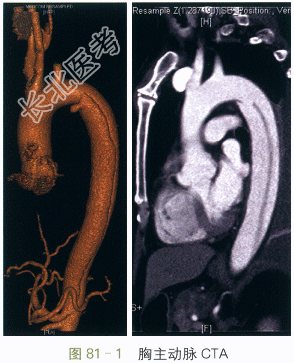

CTA扫描显示主动脉峡部内膜撕裂,可见清晰的内膜裂口和真假腔形成,范围自左锁骨下以远至

腹腔干开口水平(见图81-1)。

读片分析:本例患者CTA扫描提示主动脉峡部内膜撕裂,可见清晰的内膜裂口和真假腔形成,范围

自左锁骨下以远至腹腔干开口水平。属于主动脉夹层的典型影像学表现。由于未累及升主动脉,故解

剖学分型属于Stanford B型/DeBakeyⅢ型。